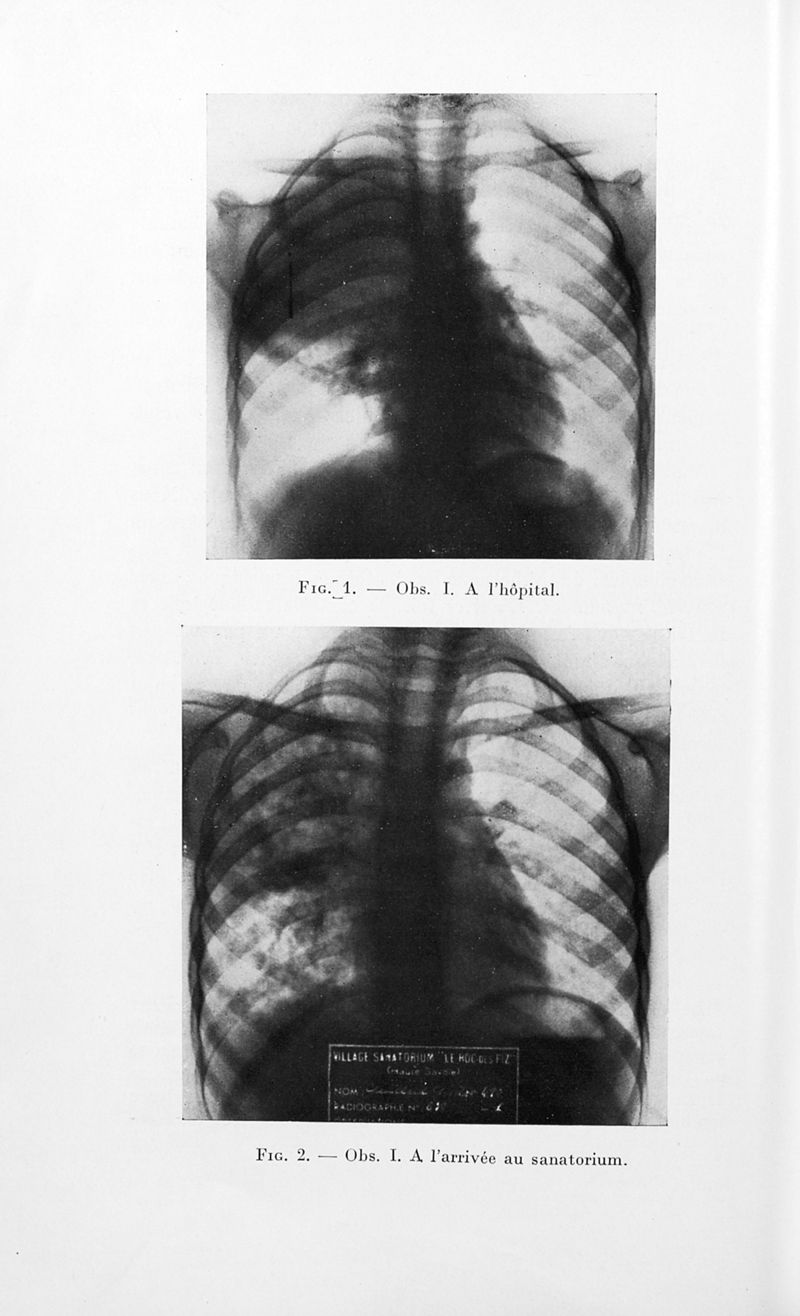

Bulletins de la société de pédiatrie de Paris

Tome trente-quatrième. - Paris : Masson et Cie, 1936.